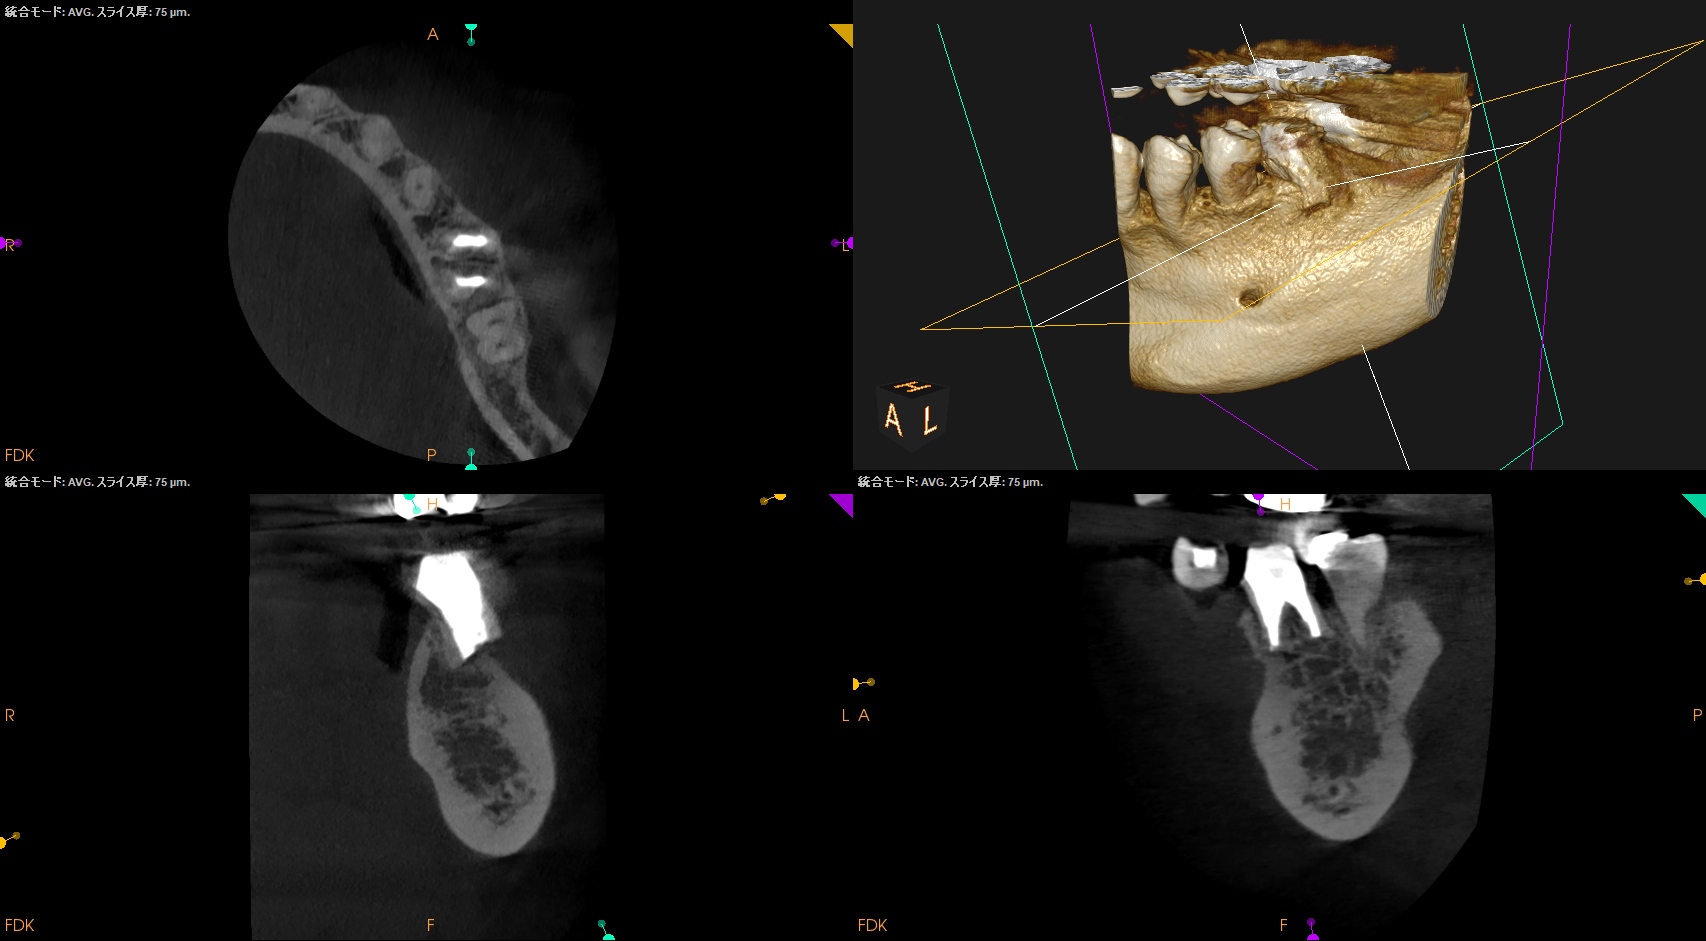

CBCT(2024.9.12)

MB

ML

D

術後にPA, CBCTを撮影した。

M

問題はないだろう。

以下のようにPA,CBCTはなった。